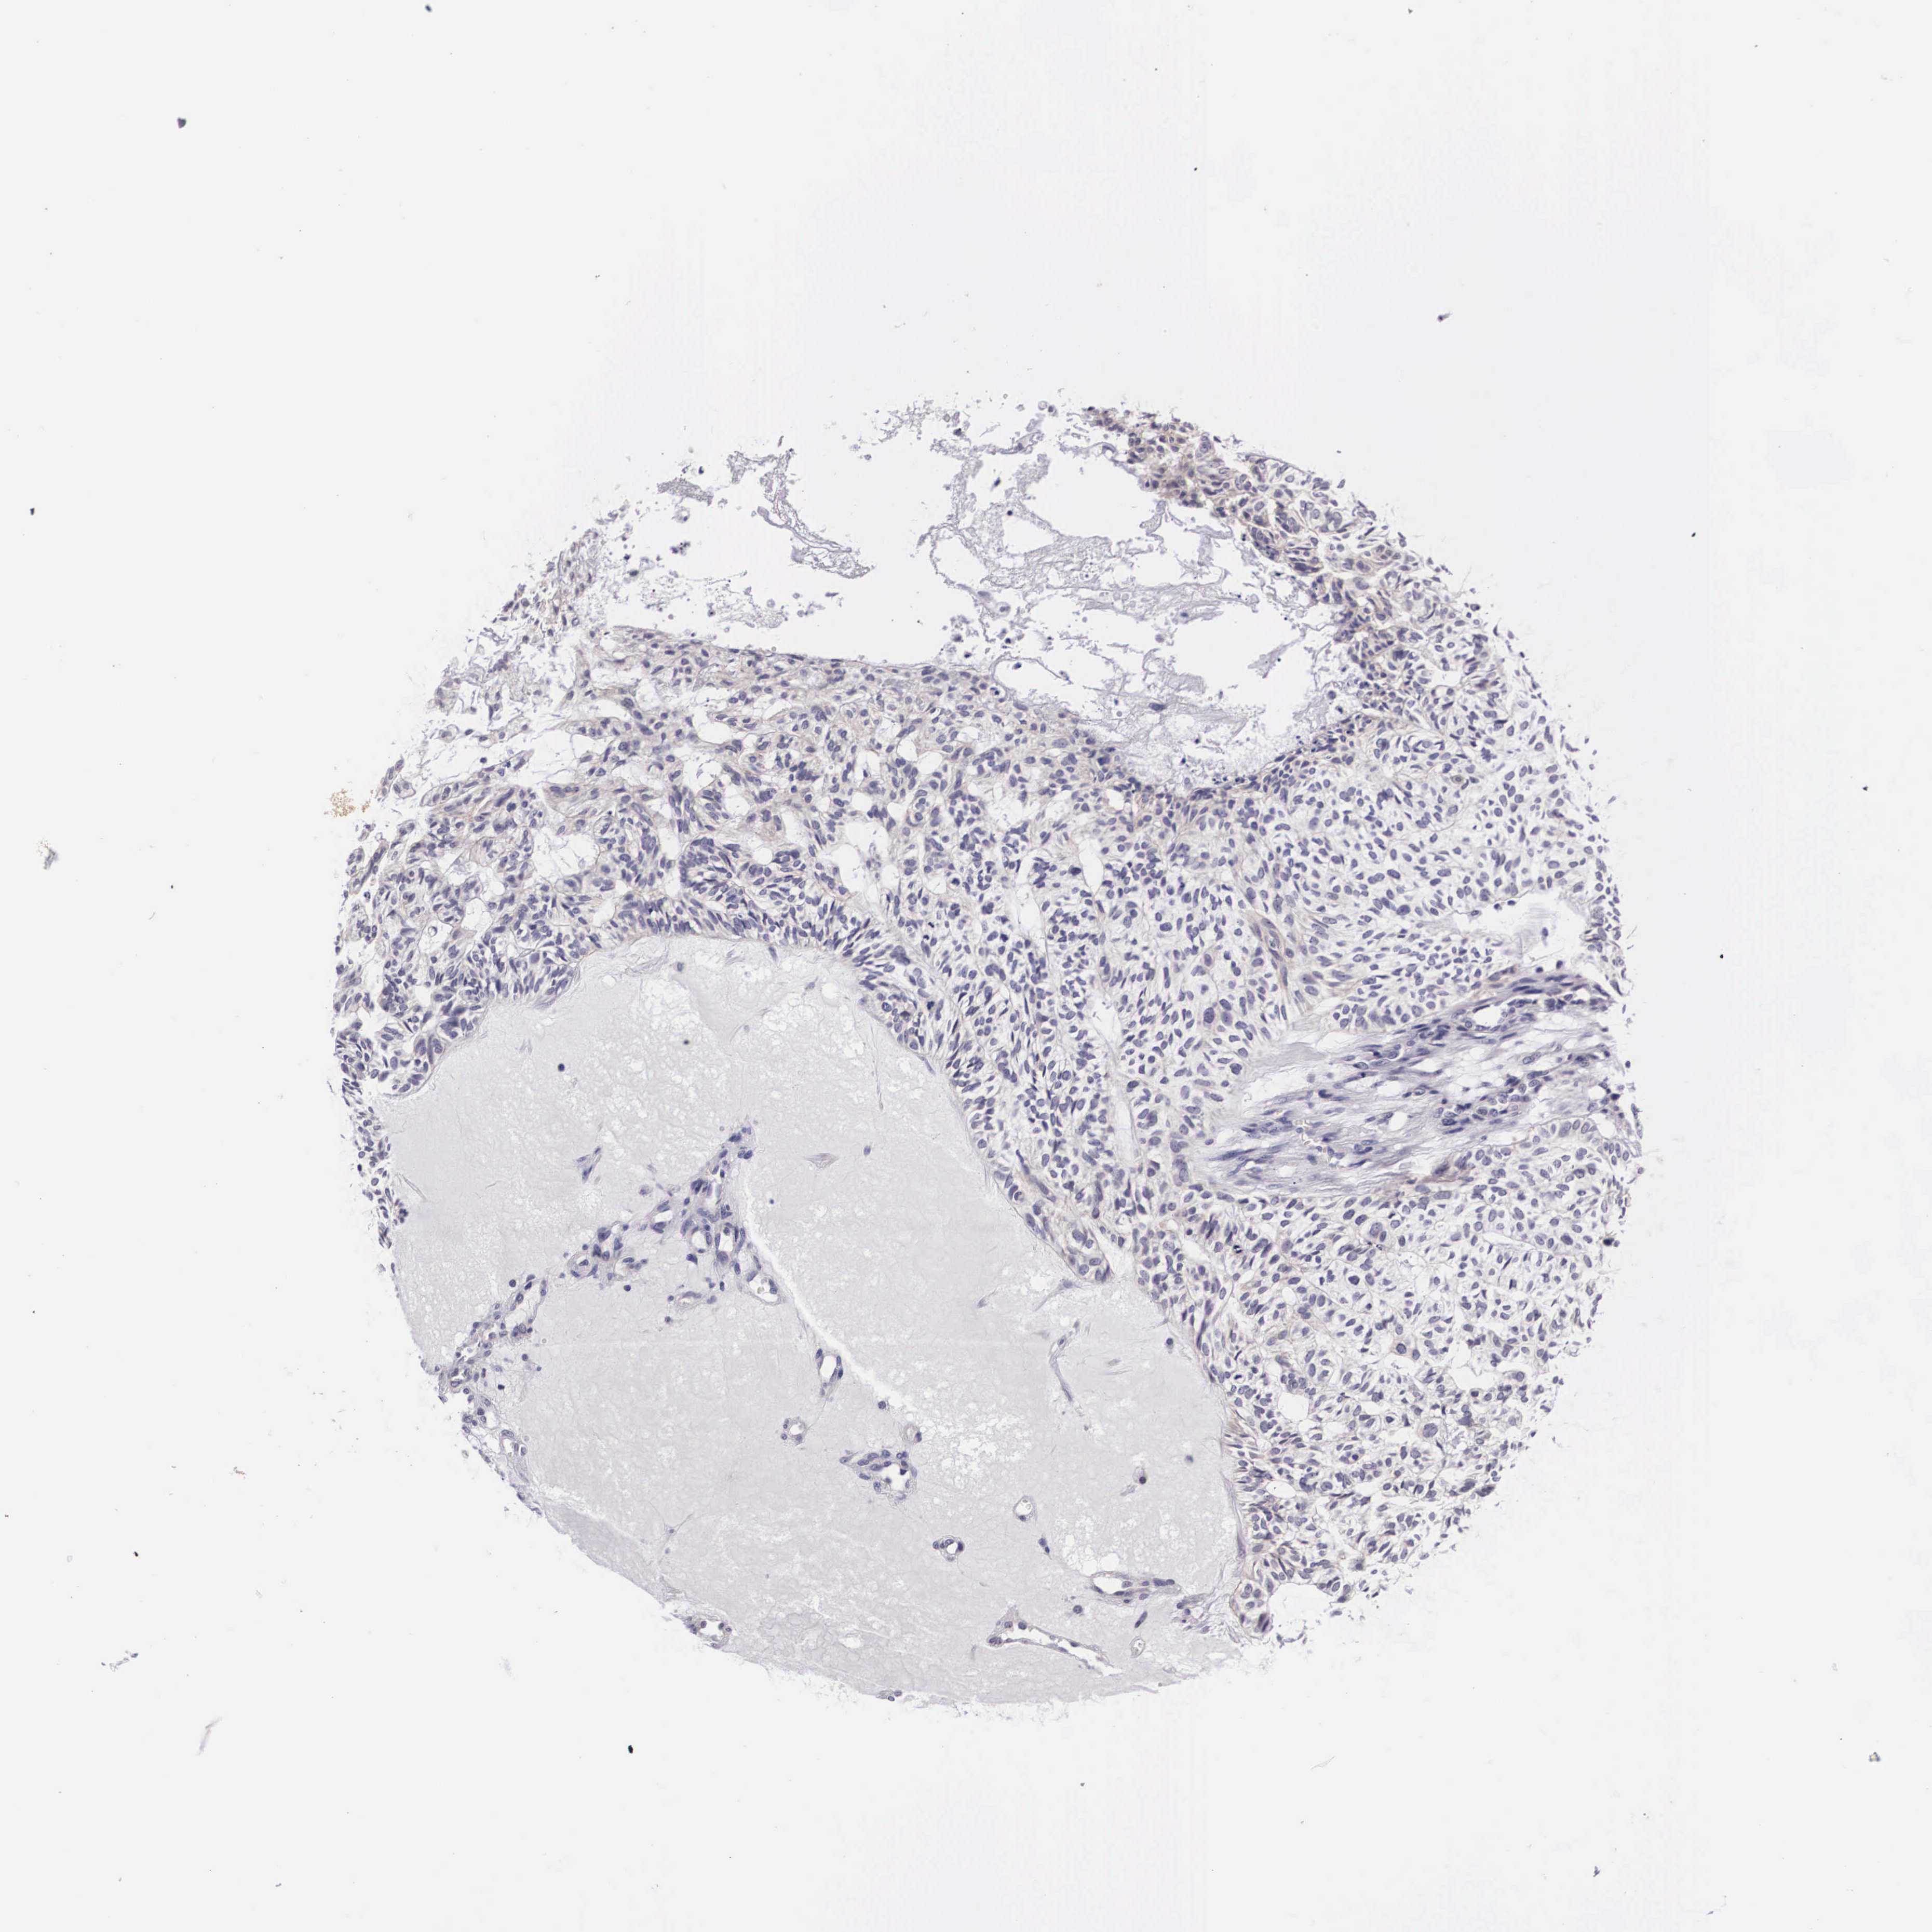

SKIN CANCER - Protein expressioni

A mouse-over function shows sample information and annotation data. Click on an image to view it in a full screen mode. Samples can be filtered based on level of antibody staining by selecting one or several of the following categories: high, medium, low and not detected. The assay and annotation is described here.

Antibody stainingi

Antibody staining in the annotated cell types in the current human tissue is reported as not detected, low, medium, or high, based on conventional immunohistochemistry profiling in selected tissues. This score is based on the combination of the staining intensity and fraction of stained cells.

Each image is clickable and will lead to virtual microscopy that enables deeper exploration of all samples and also displays staining intensity scores, fraction scores and subcellular localization as well as patient and tissue information for each sample.

Antibody HPA000647

Staining

High

Medium

Low

Not detected

Intensity

Strong

Moderate

Weak

Negative

Quantity

>75%

75%-25%

<25%

None

Location

Nuclear

Cytoplasmic/membranous

Cytoplasmic/membranous,nuclear

Squamous cell carcinoma, NOS

Basal cell carcinoma